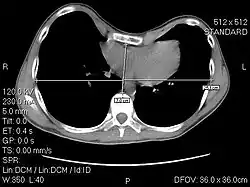

A CT scan showing a 3.58 index

The Haller index, created in 1987 by J. Alex Haller, S. S. Kramer, and S. A. Lietman,[1] is a mathematical relationship that exists in a human chest section observed with a CT scan. It is defined as the ratio of the transverse diameter (the horizontal distance of the inside of the ribcage) and the anteroposterior diameter (the shortest distance between the vertebrae and sternum).[2]

distance 1 is the distance of the inside ribcage (at the level of maximum deformity or at the lower third of the sternum)

distance 2 is the distance between the sternal notch and vertebrae.

A normal Haller index should be about 2.5. Chest wall deformities such as pectus excavatum can cause the sternum to invert, thus increasing the index.[6][7] In severe asymmetric cases, where the sternum dips below the level of the vertebra, the index can be a negative value.[8]